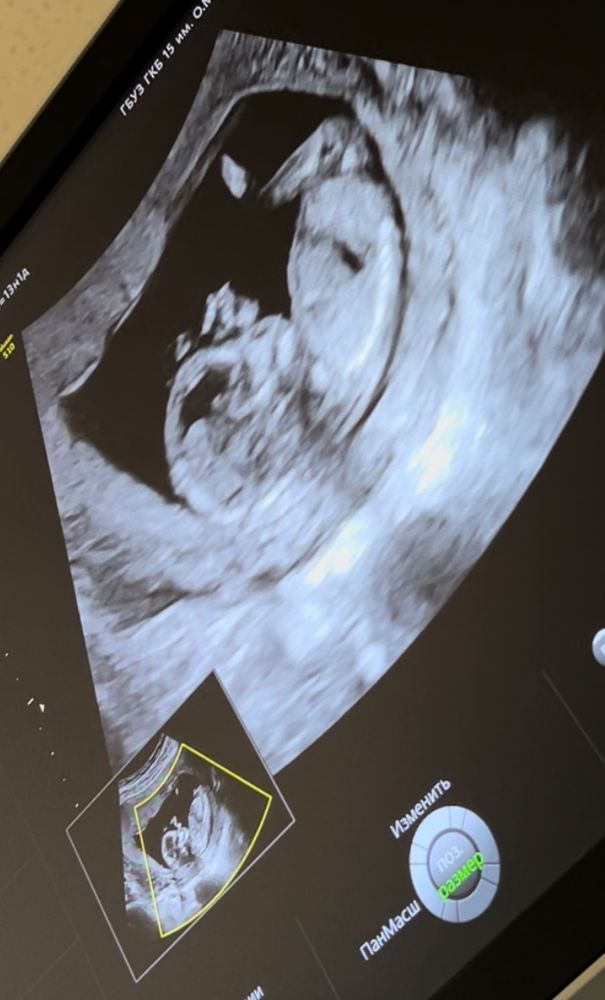

Делала скрининг в 13 недель и 5 дней, может кто поймёт по узи, прикладываю фото 🤩

Девушка....тут только гадать))) если вам узист не сказал то тут врятли кто то скажет.особенно учитывая фото по диагонали)

По форме черепа только если ) На мальчика похоже. Но бугорка не видно полового,поэтому гадания это все ))